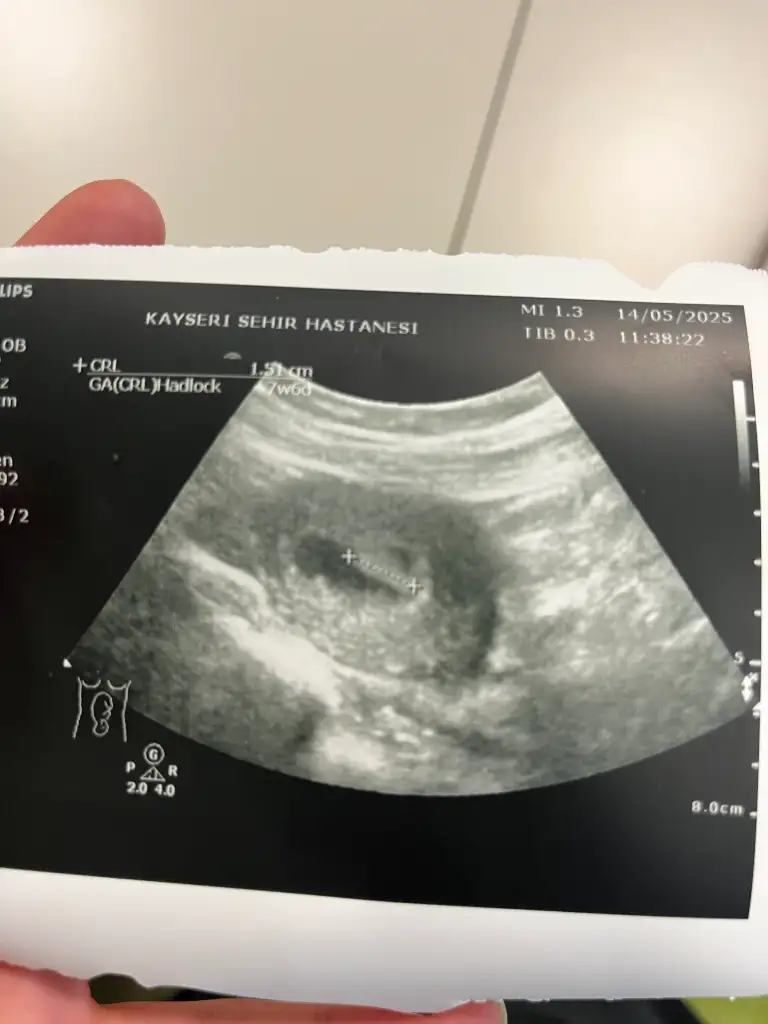

Merhabalar burda bebeğim 14 haftalık. 12 haftalıkken bir doktor kıza benziyor dedi kemik yapısı. 14 hafta başka bir doktor çıkıntı var erkek olabilir dedi alışveriş yapma bekle ama eğer bu gördüğüm pipisi değilse kızdır dedi keism gibi konuştu başta ama sonra alışveriş yapmayın 19 haftada gidince kesin söyleyecek. Sizce degisr mi cinsiyeti merak ediyorum?

Eklentiler

• 1000065546.webp

1000065546.webp

17 KB · Görüntüleme: 60